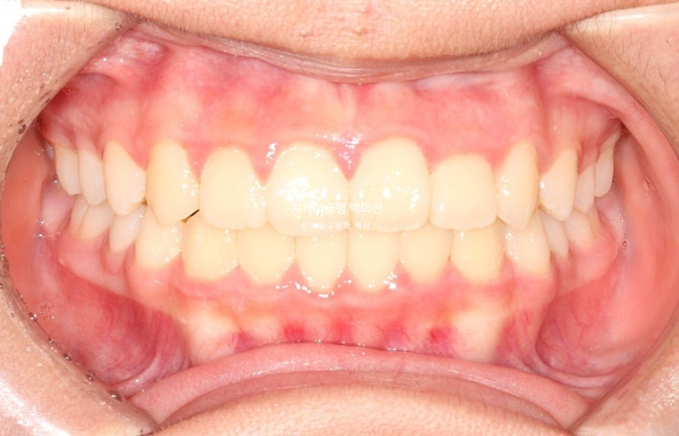

이제 전후비교 보겠습니다.

총 치료기간은 1년 6개월이며 중간에 중심선 이슈로 잠시 쉬는 시간이 4개월 있었습니다.

재제작은 총 2회 했습니다.

24.02~25.07

치료결과가 어린이 교정이 아닌, 정식 성인교정 치료 결과에 준하는 만큼 유지장치도 철저하게 들어갑니다.

어긋난 중심선이 맞아졌으며 기울어진 앞니 치축도 좋아졌습니다.

앞니가 깊게 물리는 과개교합도 좋아졌습니다.